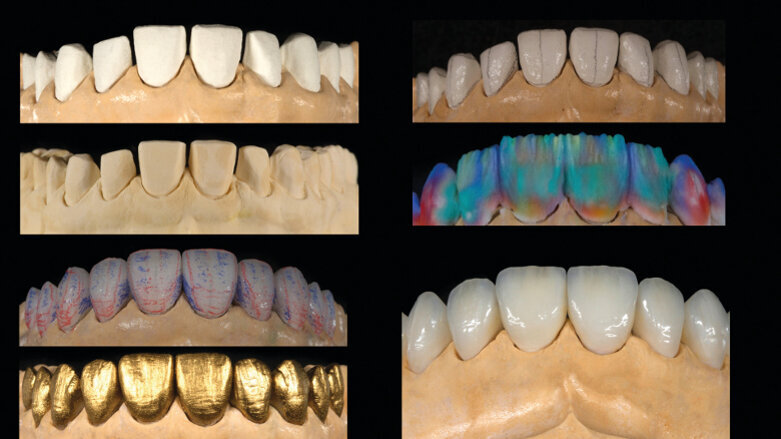

Fig. 13 : Flux de travail analogique (modèles positifs unitaires réfractaires, fabrication des facettes, ajustements, coloration/glaçage).

Fig. 14 : Flux de travail numérique (modèle imprimé en 3D, facettes réalisées en technique CFAO, ajustements, coloration/glaçage).

Le jeu de facettes en céramique feldspathique a été fabriqué en IPS Style (Ivoclar Vivadent) sur un modèle en plâtre-pierre, tandis qu‘un bloc IPS Empress CAD Multi (Ivoclar Vivadent) a été utilisé pour le jeu numérique (Figs. 13 et 14). Les deux jeux ont été évalués en bouche avec une pâte d‘essai afin de comparer les propriétés optiques des facettes feldspathiques et des facettes réalisées en technique CFAO (Figs. 15a–c).